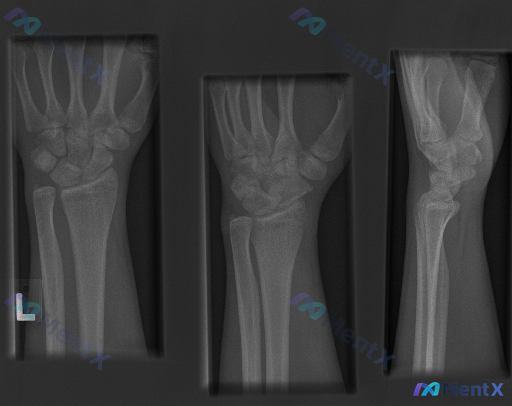

大家好,今天我们来讨论一份左侧腕部外伤后的X光片资料。先给大家看一下三个体位的影像学观察结果: 1. 放射影像-手腕处X光片-正位 (AP View) 骨骼完整性: 桡骨远端: 桡骨远端干骺端见明显骨折线,皮质连续性中断,呈现典型的背侧移位(Colles骨折特征),伴有明显的背侧成角和嵌插表现。桡骨...